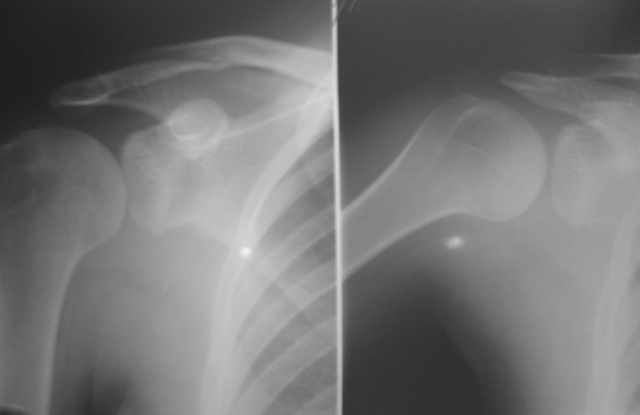

Пациентка 18 лет страдает привычным задним вывихом плеча. Выполнены операции: Задний

артрориз с использованием аутотрансплантата, рцидив выввиха через 6 мес после операции

(клинически и рентгенологически трансплантат рассосался). Остеотомия суставного

отростка лопатки с увеличением угла антеверсии, рецидив через 9 мес. Какие варианты

стабилизации возможны в данном случае? На рентгенограмме справа плечо в положении вывиха.